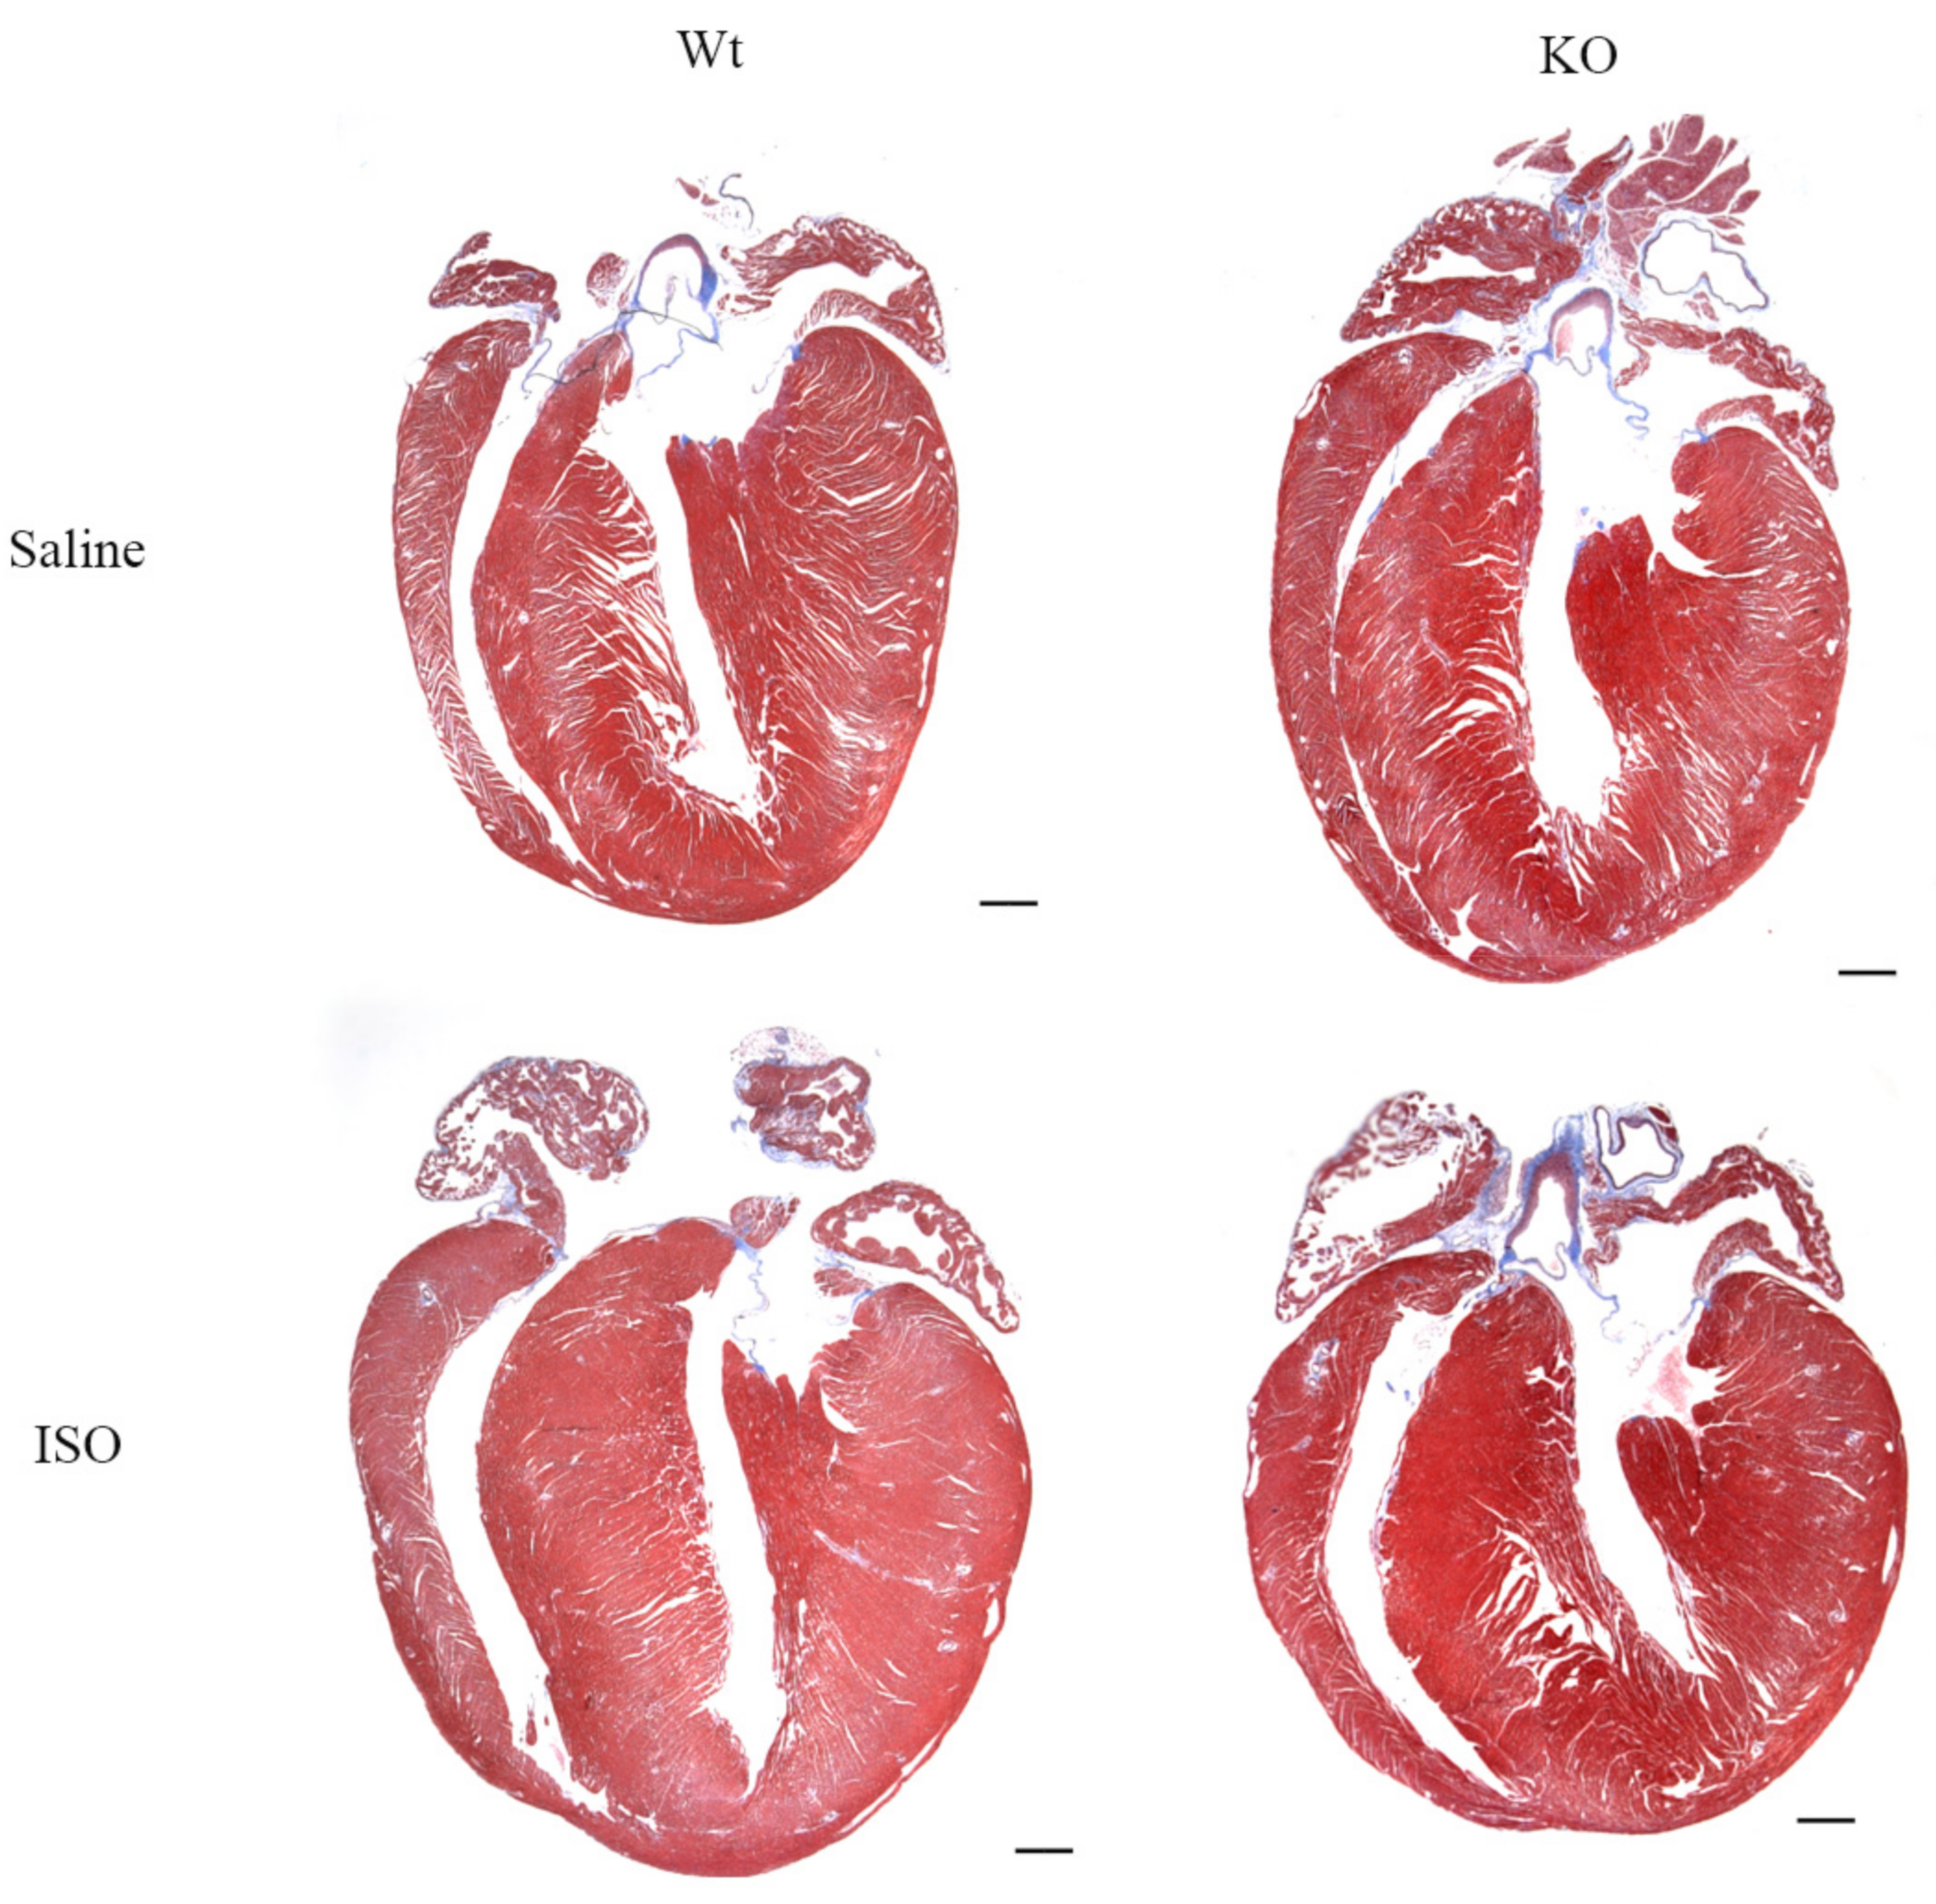

3.5. Impact of Isoproterenol Induced Stress on SLMAP3-KO Hearts